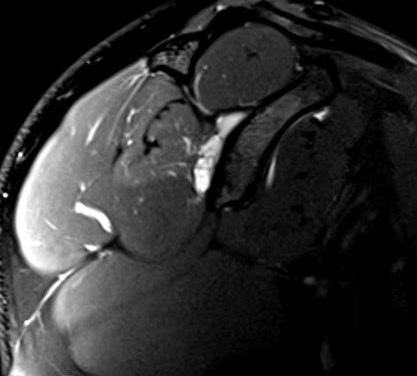

Figura 1: Secuencia sagital T1-FS: adecuada distensión de la cápsula articular tras la administración directa de medio de contraste bajo guía ecográfica.

Figura 2: Secuencia axial PD-FS: quiste bilobulado en la escotadura espinoglenoidea.